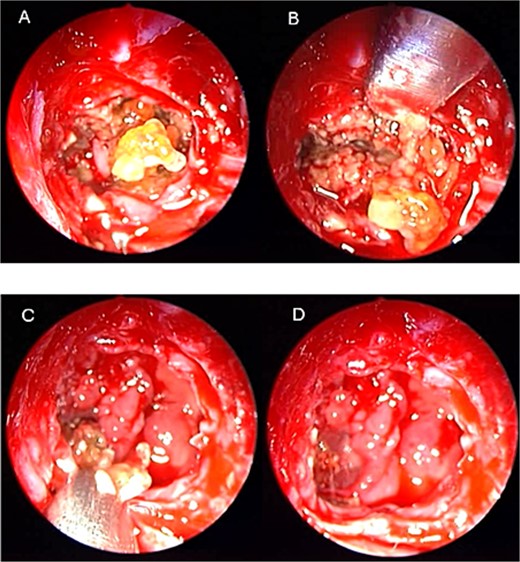

A 36 years-old man with no previous history of medical disease presented to the otolaryngology clinic with a chief complaint of headache that was associated with pressure feeling mainly in the occipital area. He also reported a post-nasal drip. The patient underwent a non-contrast paranasal sinus CT scan (Fig. 1) that demonstrated an isolated sphenoid sinus homogenous opacification, most likely representing sphenoid fungal ball. A decision was made to proceed with endoscopic sphenoidotomy (Fig. 2) to clean and remove the debris, which confirmed the diagnosis of sphenoid sinus fungal ball.

Coronal (A) and axial (B) images of a nonenhanced CT scan of the paranasal sinuses showing left sphenoid sinus complete homogenous opacification.

Intra-operative (A and B) endoscopic sphenoidotomy showing fungal debris, with post-operative examination (C) showing clean wide sphenoid sinus free from fungal debris.